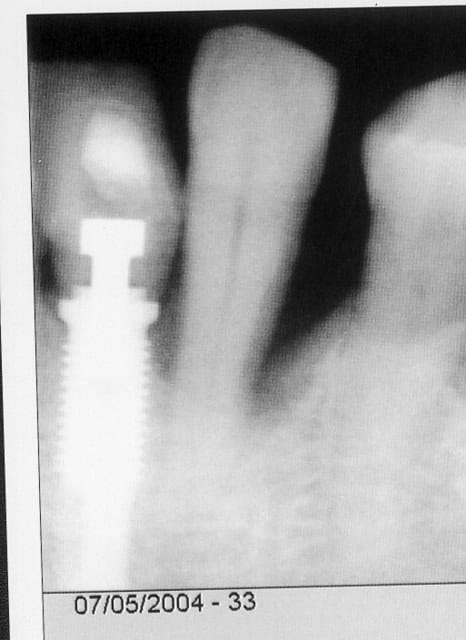

alors c'est un cas d'implant dans une bouche dégueulasse??? mais mon pauvre con, tu ne sais pas ce qu'est un implant, et tu ne sais même pas ce qu'est un patient visiblement. lorsqu'on remplace une dent par un implant, comme dans ce cas, pour des raisons parodontales, nous avons affaire à des gens porteurs d'une pathologie dont les causes ne disparaissent pas du jour au lendemain, ça c'est la dentisterie de tout les jours, c'est un cas de tous les jours, et tu veux peut-être un coup de karcher juste avant pour que ça brille?? pour épater la galerie?? est-ce que tu sais simplement comment réagit un implant dans un contexte parodontal?? regarde bien la radio de l'implant le jour de sa pose, et regarde ensuite la radio 3 ans après, en sachant que la patiente ne s'est pas pliée aux éxigences de la maintenance, tu vois quoi, gros con? un implant explosé? perdu? ne me réponds pas, tu le fera quand tu auras fait ton premier cas d'implants.

Comment éxplique tu une telle rétraction de la chambre pulpaire de 33 en 3 ans ?

14/12/2004 à 00h19

Sur les 2 radios l'incidence n'est pas la même, la cavité pulpaire est plus volumineuse en vestibulo-lingual d'où l'image de la 1è radio, alors que sur la 2è la 33 est centrée d'où une cavité pulpaire effilée mais NORMALE!!!!